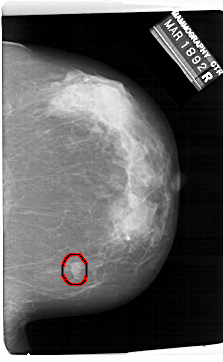

A_1414_1.RIGHT_MLO

RIGHT_MLO LINES 6796 PIXELS_PER_LINE 4276 BITS_PER_PIXEL 12 RESOLUTION 43.5 OVERLAY

FILE: A_1414_1.RIGHT_MLO.OVERLAY

TOTAL_ABNORMALITIES 1

ABNORMALITY 1

LESION_TYPE MASS SHAPE OVAL MARGINS ILL_DEFINED

ASSESSMENT 4

SUBTLETY 3

PATHOLOGY BENIGN

TOTAL_OUTLINES 1

BOUNDARY